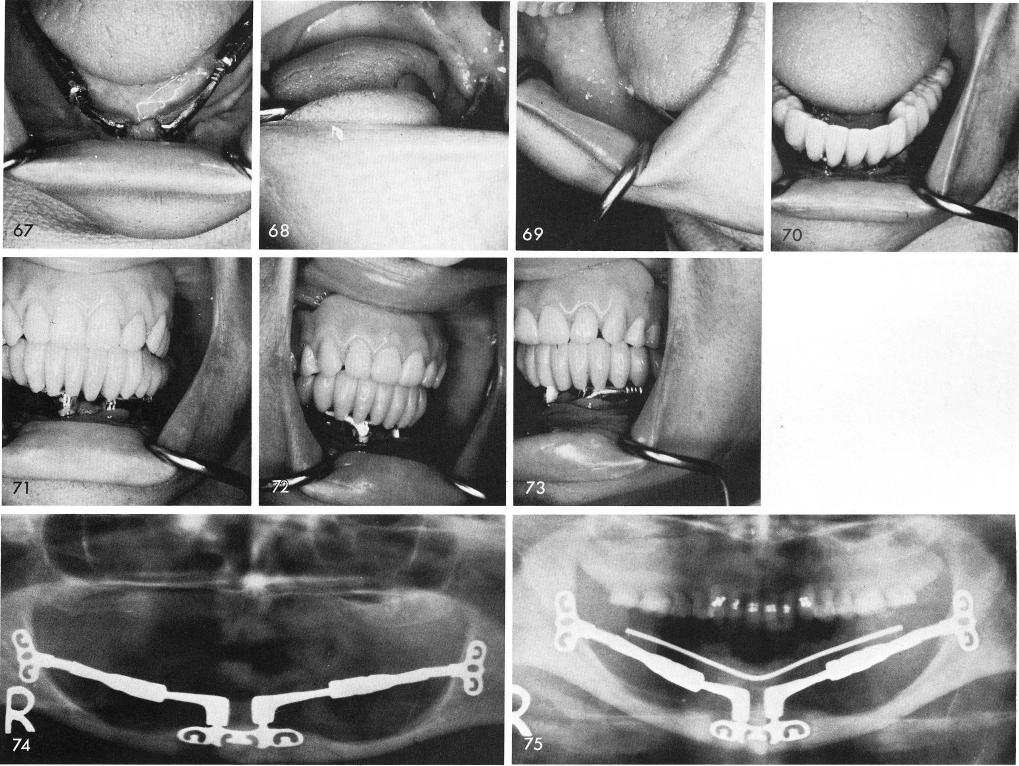

were removed, figs. 67, 68, 69, and the final acrylic prosthesis was processed, figs. 70, 71, 72, 73. The post-operative x-ray without and then with the fixed all acrylic prosthesis, figs. 74, 75.

1 X-rays without and with acrylic prosthesis on symphyseal ramus system